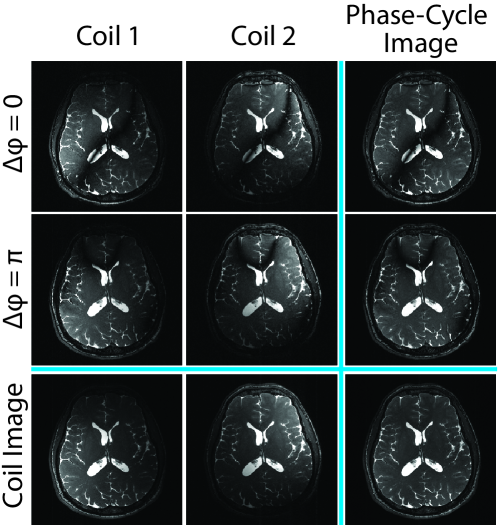

Here, we propose an improved framework for phase-cycled bSSFP imaging, reconstruction by calibration over tensors (ReCat), that utilizes correlated information simultaneously across multiple coils and acquisitions (Fig. 1). ReCat is based on a joint encoding model: the bSSFP image for a given coil and phase-cycle is taken to be spatially modulated by a respective pair of coil sensitivity [11, 21] and bSSFP profile [22, 17]. A tensor-interpolation kernel comprising coil and acquisition dimensions is estimated from calibration data. This kernel is then used to linearly synthesize unacquired samples. Compared to kernels trained only on coil or on phase-cycles, the ReCat kernel aims to optimize use of aggregate information across both dimensions.

under the assumption that the echo time (TE) is one half of the repetition time (TR). Here, denotes the signal captured by the coil element ( [1 D]) and the acquisition ( [1 N]). is the coil sensitivity, is the phase increment, and is the phase accrued due to off-resonance (assumed to be constant across acquisitions). Note that , , are terms that do not depend on off-resonance or phase increments. With equispaced across , banding artifacts in separate bSSFP images will be largely nonoverlapping [28]. Thus multiple phase-cycled bSSFP images can be combined to effectively suppress banding artifacts [3, 7]. However, to maintain scan efficiency, each phase-cycled acquisition should first be undersampled by a factor of R, and images must be recovered during subsequent reconstructions.

All reconstruction methods produced separate images from each acquisition and each coil. Individual images were then combined with the p-norm method to maintain favorable performance in artifact suppression and SNR efficiency [31]. Combination was performed with across coils, and with across acquisitions (see Sup. Fig. S2). Two different orders of combination were tested: first across coils then acquisitions, and first across acquisition then coils. No significant difference was observed due to combination order.